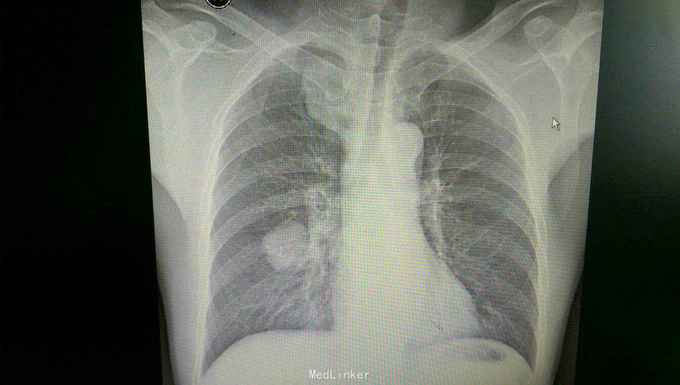

患者入院后,拟行左颌下肿块切除,在术前检查,术前准备时,常规胸片发现右侧肺部肿块,进一步行颈部及胸部ct检查,提示左颌下淋巴结肿大,转移性可能。右下肺周围性肺癌伴右肺门及纵膈多发淋巴转移考虑。决定先行左颌下肿块切除,明确诊断。术后病理示:左(左颌下腺)淋巴结转移性癌,来源首先考虑为肺。患者及家属考虑为晚期肿瘤,拒绝进一步手术治疗及化疗,下颌部切口愈合拆线后,出院。